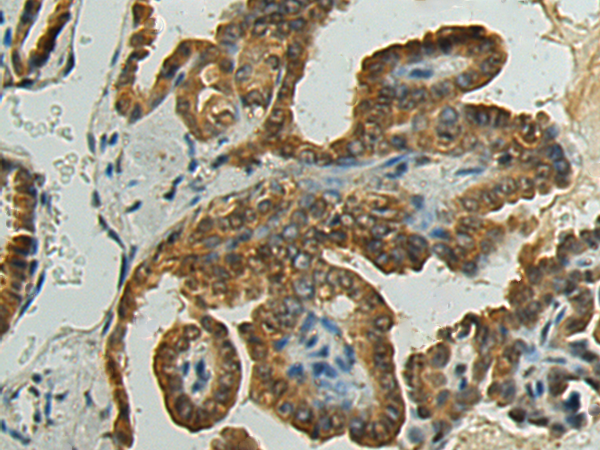

分类: 科研抗体货号: P09868别名: HPRT; HGPRT应用: WB,IHC反应种属: Human, Mouse, Rat